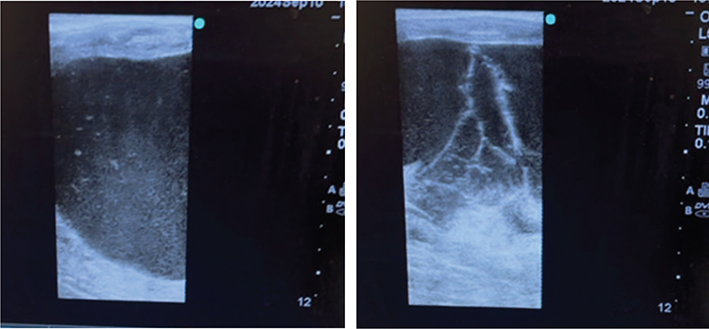

Due to the persistence and continued growth of the structure on the left ovary combined with the results of the GCT panel, the decision was made to remove the left ovary. Transrectal ultrasonography was conducted before surgery. What was earlier described as an anechoic follicular structure appeared hyperechoic and had hyperechoic strands (Figure 1). Standing unilateral left ovariectomy was performed with a flank approach. Ovary had to be drained (500 ml of fluid was drained via suction) before removal. Ovary was large (~ 10 x 5 cm) and had a well demarcated unencapsulated mass (Figure 2); there was hemorrhage within its stroma. Ovary was submitted for histopathology.9

Figure 1.

Figure 1. Transrectal ultrasonographic images of the abnormal structure on the left ovary immediately prior to ovariectomy. Both images are from the same evaluation of the structure but are different planes of view; note the hyperechoic appearance of the antral fluid in some fields and thin hyperechoic strands in others (only 12 cm depth is depicted, but the structure extended beyond this field)